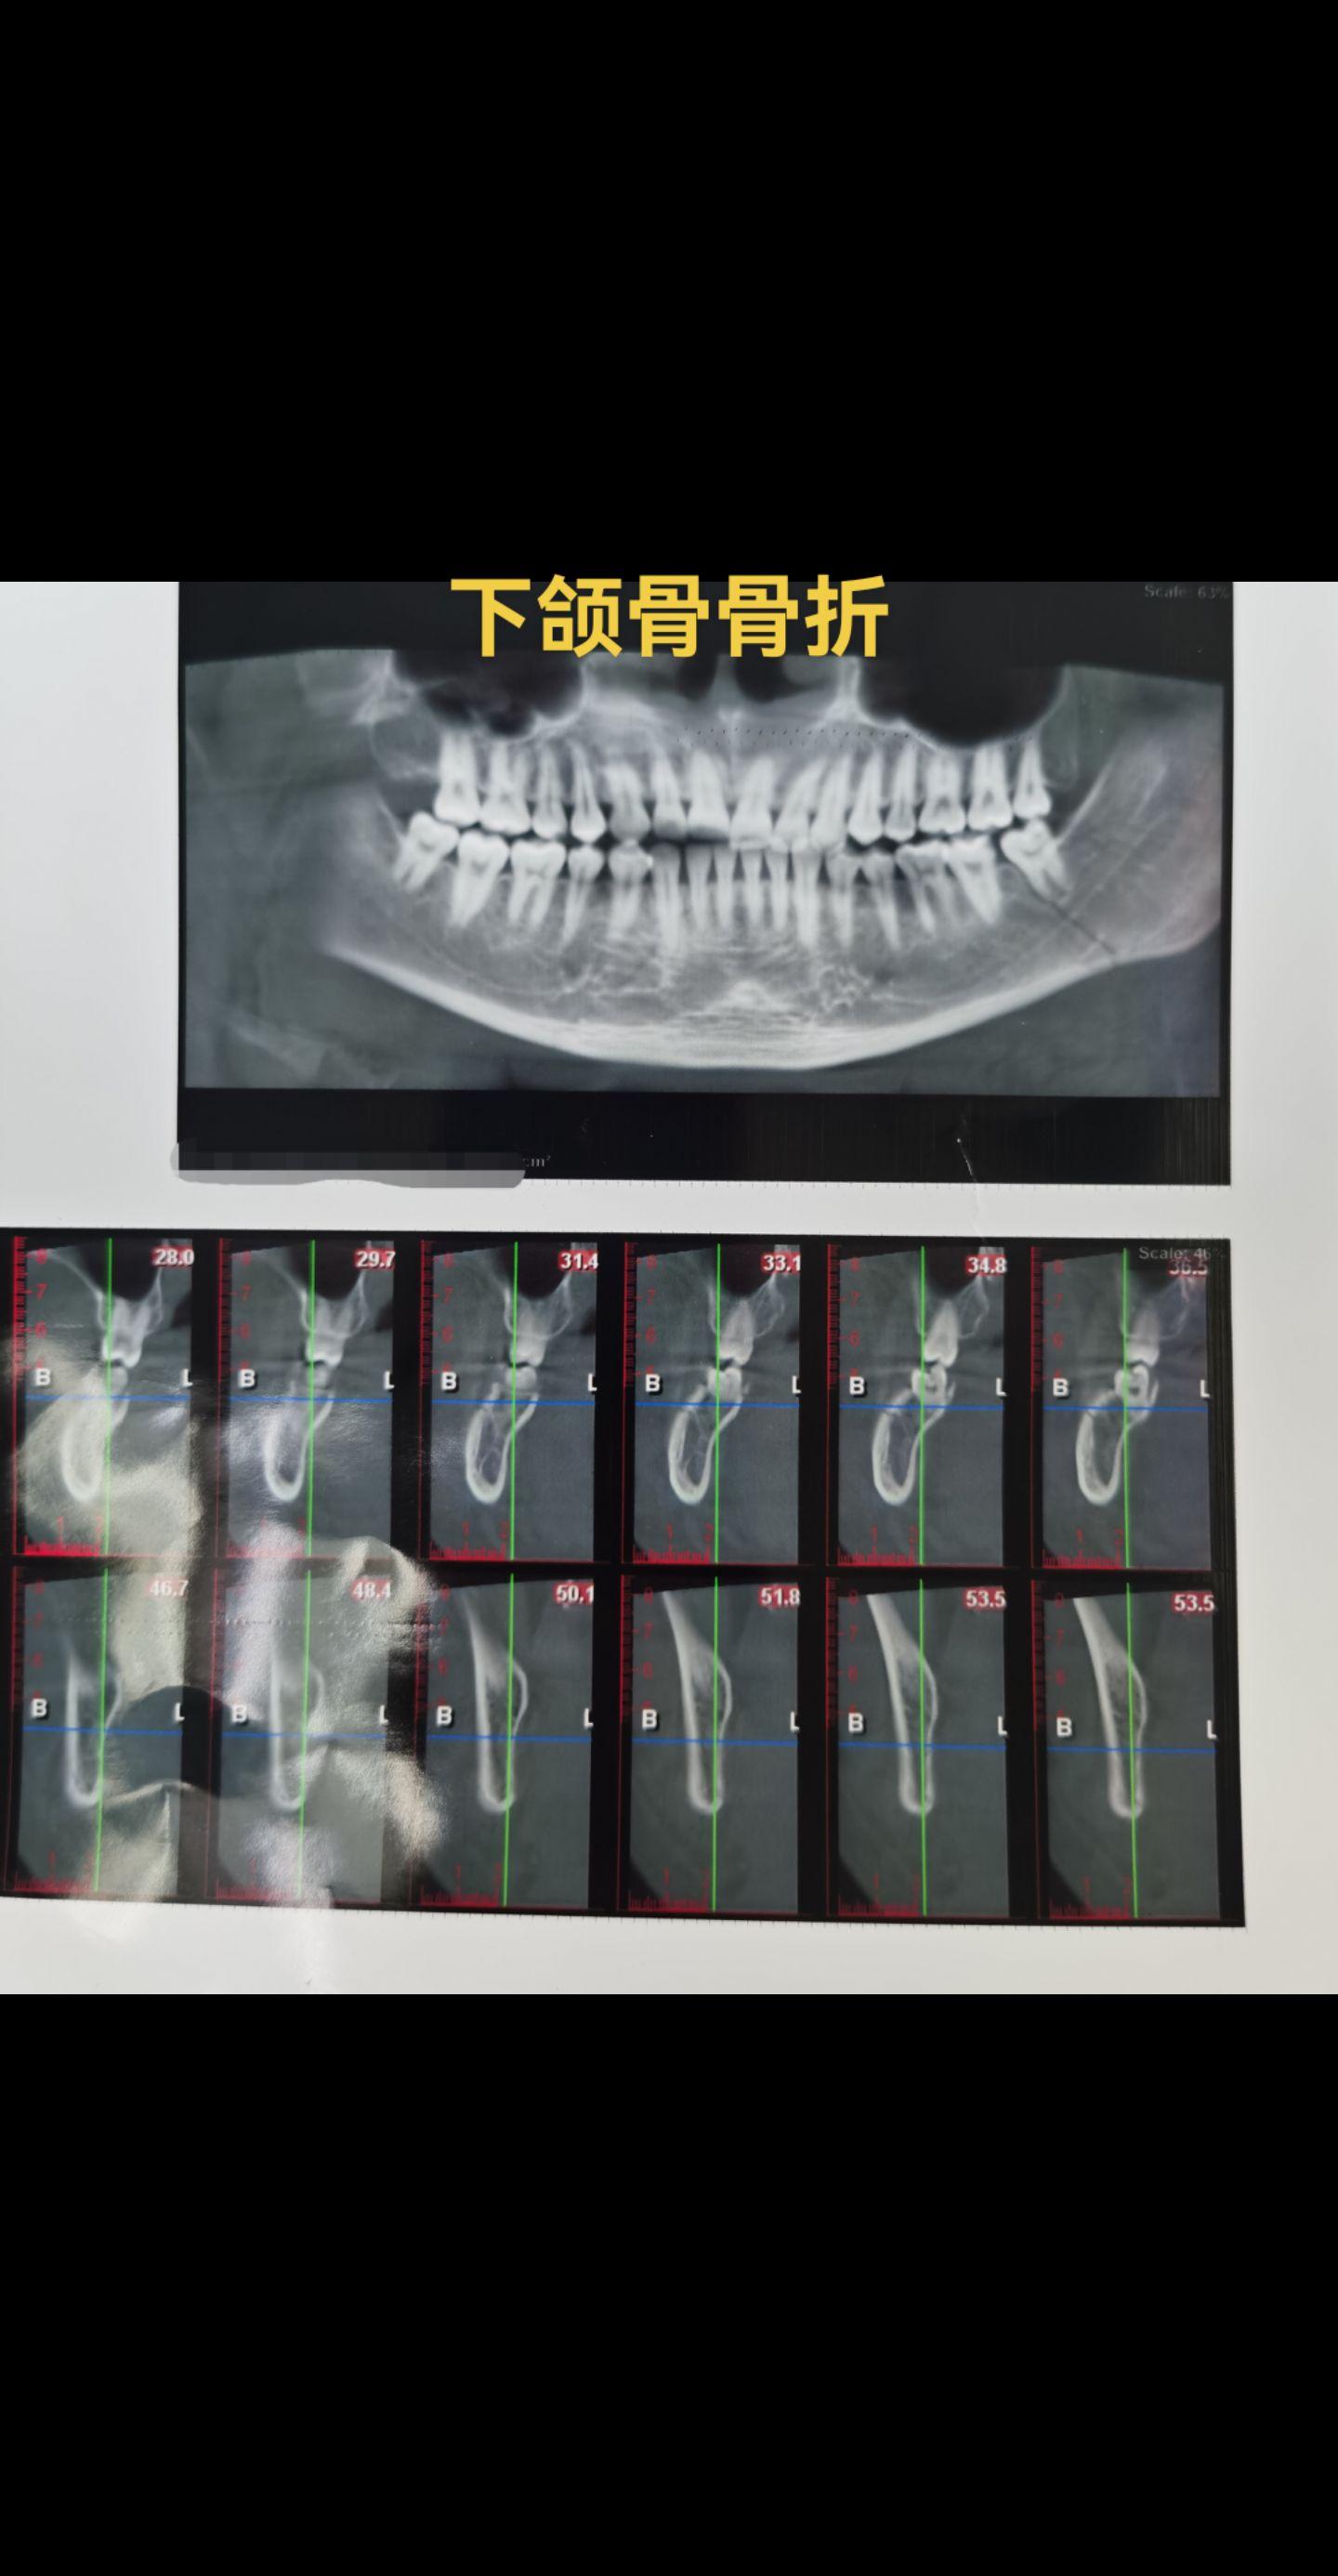

下颌骨骨折。下颌骨骨折的主要临床表现:咬合紊乱;功能障碍;面部畸形。